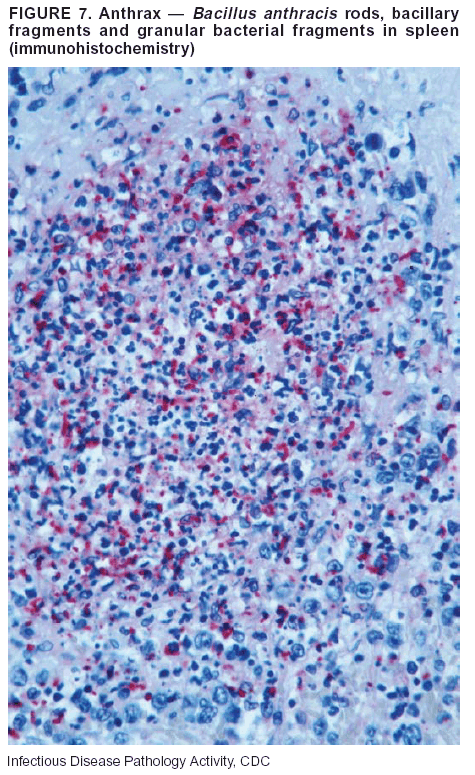

Diagnostic Tests. If the patient has not received antibiotics, bacilli can be observed in tissues with H&E, Gram, and silver impregnation stains and IHC assays (Figures 6 and 7). However, after antibiotic treatment has been instituted, only silver stains and IHC assays will highlight the bacilli. IHC assays for B. anthracis can demonstrate bacilli, bacillary fragments, and granular bacterial fragments in formalin-fixed tissues, even after 10 days of antibiotic treatment. Although a DFA test is available for B. anthracis, it is not used on formalin-fixed tissues.